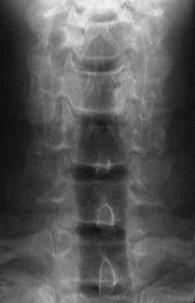

FRACTURA - LUXATIE T12 FRACTURA COMPLEXA DE COLOANA

VERTEBRALA LOMBARA